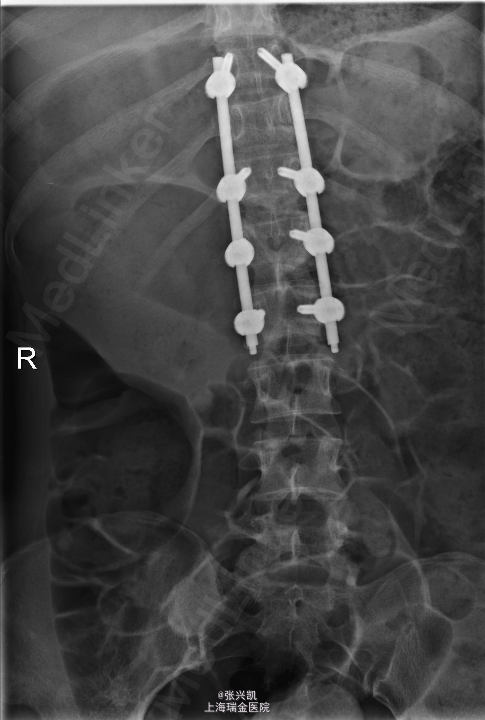

诊断:多发胸腰椎骨折(T11,L1) 处理:胸腰椎骨折经皮椎弓根钉复位内固定术,一年后骨折愈合良好,行内固定装置取出术

随访:术后三月复诊,内固定装置位置良好,患者腰背痛症状缓解,一年后骨折愈合,行内固定装置取出。术后患者腰部活动良好 讨论:术后应积极锻炼腰背部肌肉,防止萎缩。